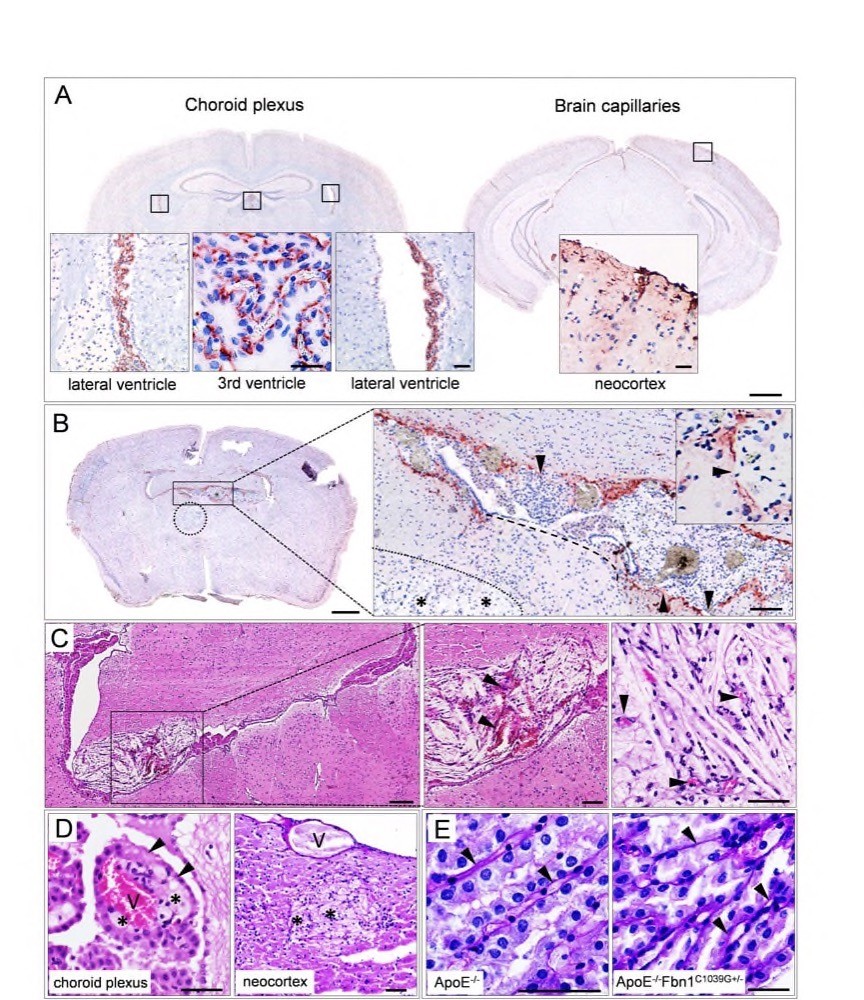

Chapter 4 Figure 6Fibrillin-1 is expressed in the choroid plexus and capillaries of the neocortex, corresponding with the capillary basement membrane. (A) Brain sections showing presence of fibrillin-1 in the choroid plexus of the lateral and third ventricles (left hand panel) and capillaries of the neocortex (right hand panel). (B) Fibrillin-1 stain showing that in the presence of a xanthoma, the choroid plexus appears damaged and fenestrated (arrowheads in the high magnification image) or even completely disappears (dashed line), allowing the growth of the lesion into the parenchyma (xanthomas are indicated with dotted lines, foam cells and cholesterol clefts with asterisks). (C) HE stain showing haemorrhage (arrowheads) and small blood vessels in a xanthoma in the lateral ventricle (left hand and middle panel) and neocortex (right hand panel), respectively. (D) Early development of a xanthoma in the choroid plexus. Foam cells (asterisks) are observed around a (capillary) vessel (V) in the choroid plexus, damaging the epithelium (arrowheads, HE stain, left hand panel). The right hand panel shows the extravasation of foam cells adjacent to a blood vessel in the neocortex (PAS stain). (E) PAS stain showing an organized (ApoE-/-, left hand panel) or damaged (ApoE-/-Fbn1C1039G+/-, right hand panel) structure of the choroid plexus. The basement membrane (arrowheads) appears to be thicker in ApoE-/-Fbn1C1039G+/- compared to ApoE-/-mice. Scale bar=50µm (high magnification images in A and C, D, E), 200µm (B, C) and 1mm (low magnification brain images in A, B).